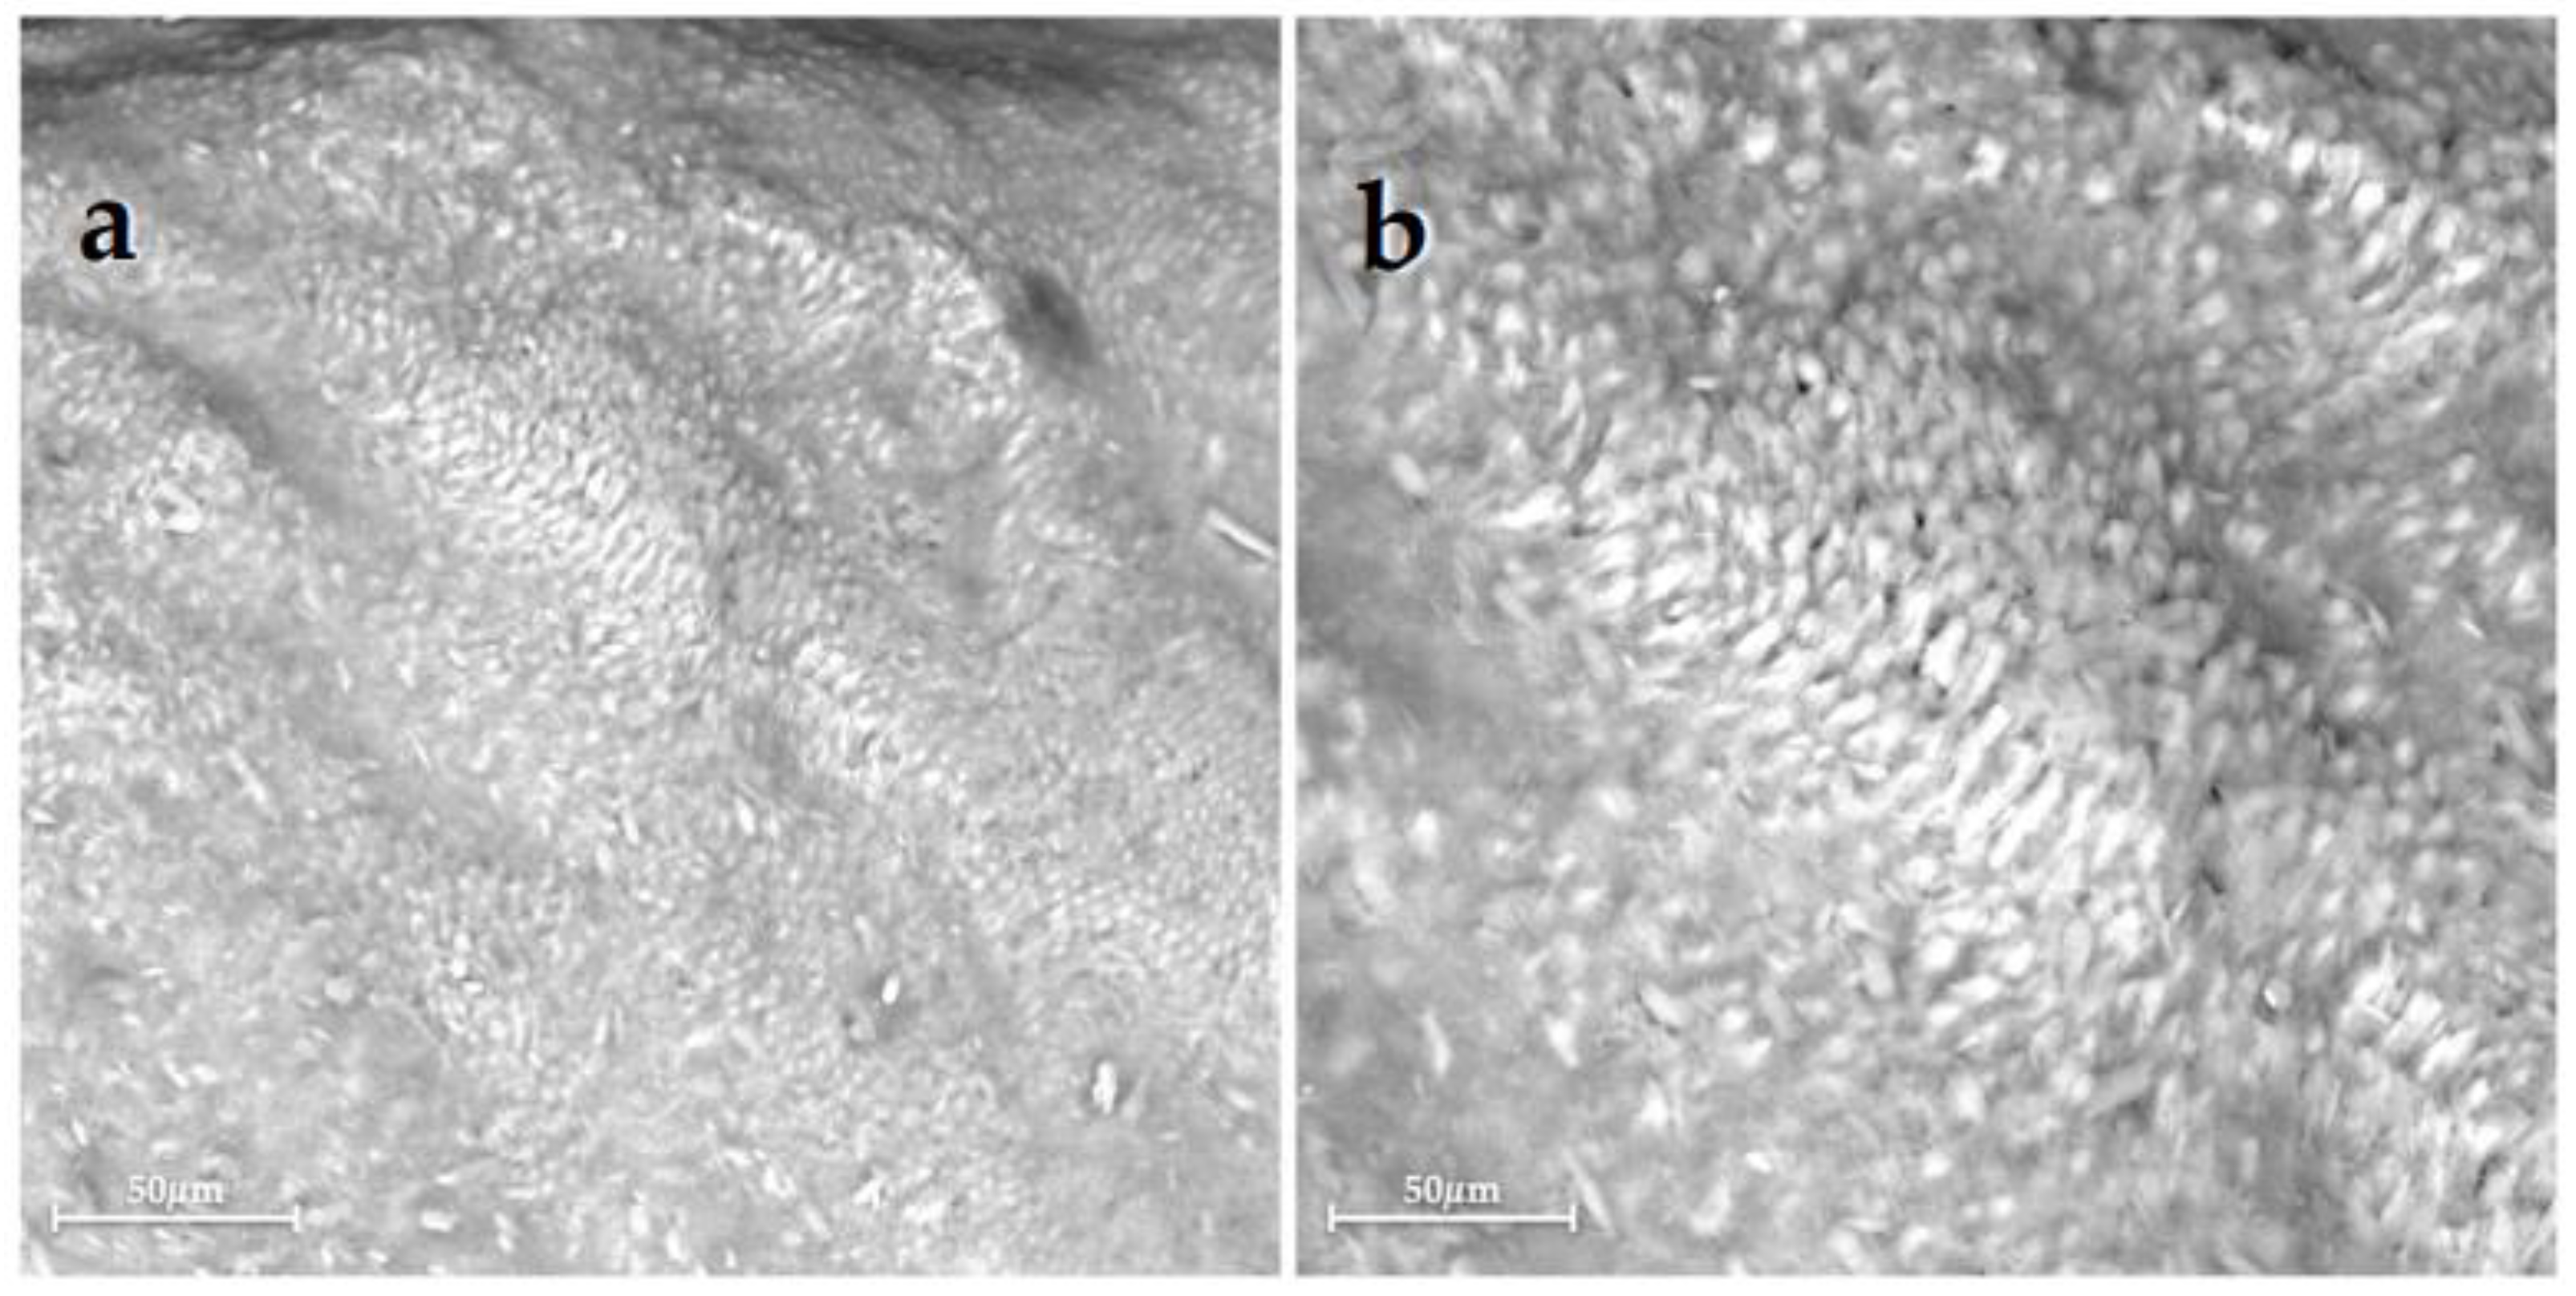

2.4. SEM-EDX Analysis